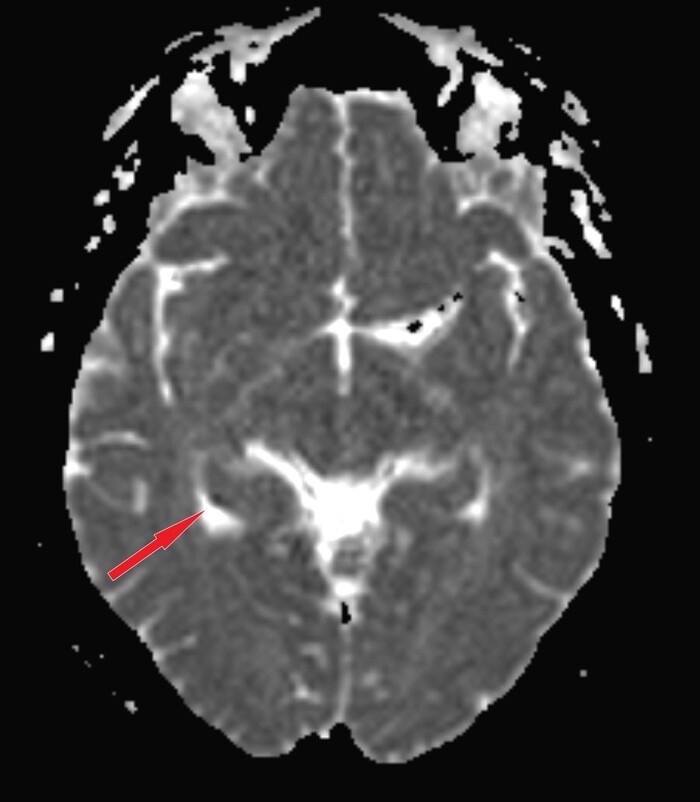

Само МРТ головного мозга тоже особых изменений не выявило, за исключением "светящейся точки" на DWI-изображениях с коррелатом на диффузионной карте:

что встречается при транзиторной глобальной амнезии (ТГА):

Kлинический синдром, характеризующийся внезапно возникшим эпизодом амнезии (антероградной, частично ретроградной), продолжительностью менее 24 часов без каких-либо других неврологических симптомов. В большинстве случаев симптомы полностью исчезают в течение нескольких часов после появления.

Частота ТГА составляет приблизительно 5–10 на 100 000 населения, обычно встречается у пациентов старше 50 лет, немного чаще у женщин.

Этиология ТГА остается не полностью понятной с различными гипотезами относительно её причины, включающими ишемию, эпилепсию, мигрень и венозный застой.